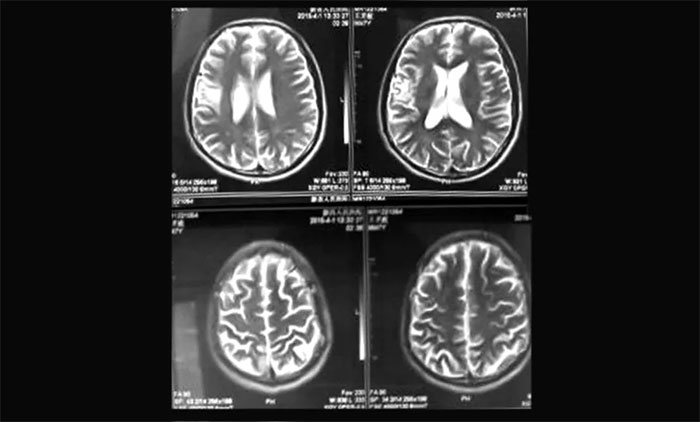

▲ 磁共振影像提示右颞顶动静脉畸形

上海蓝十字脑科医院肿瘤科(放疗)头部伽玛刀组主任陈琦曾收治一位青年男性AVM患者胡某(化名)。该患者曾因头晕头痛、口齿不清在当地医院就医,影像检查提示“右颞顶占位”,考虑为脑肿瘤可能性大,采取药物对症治疗。其后,患者因前额顶部位胀痛找到陈琦主任团队寻求进一步治疗方案。通过影像学检查,提示病灶区域潜在血管异常,诊断排除脑肿瘤,而是右颞顶动静脉畸形。